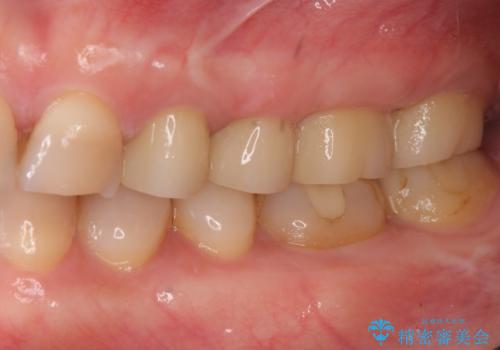

虫歯の深化により根管治療、歯周外科手術を行い歯肉の状態を改善し精密なセラミッククラウンを製作する治療を計画します。

- 50万円(仮歯・ファイバーコア・ジルコニアクラウン×4 歯周外科)費用は治療当時の料金となります

セラミック治療の長期的な予後を見込むために、根管治療、歯周外科を行いクラウン装着前の環境を整えておくことが肝要です。